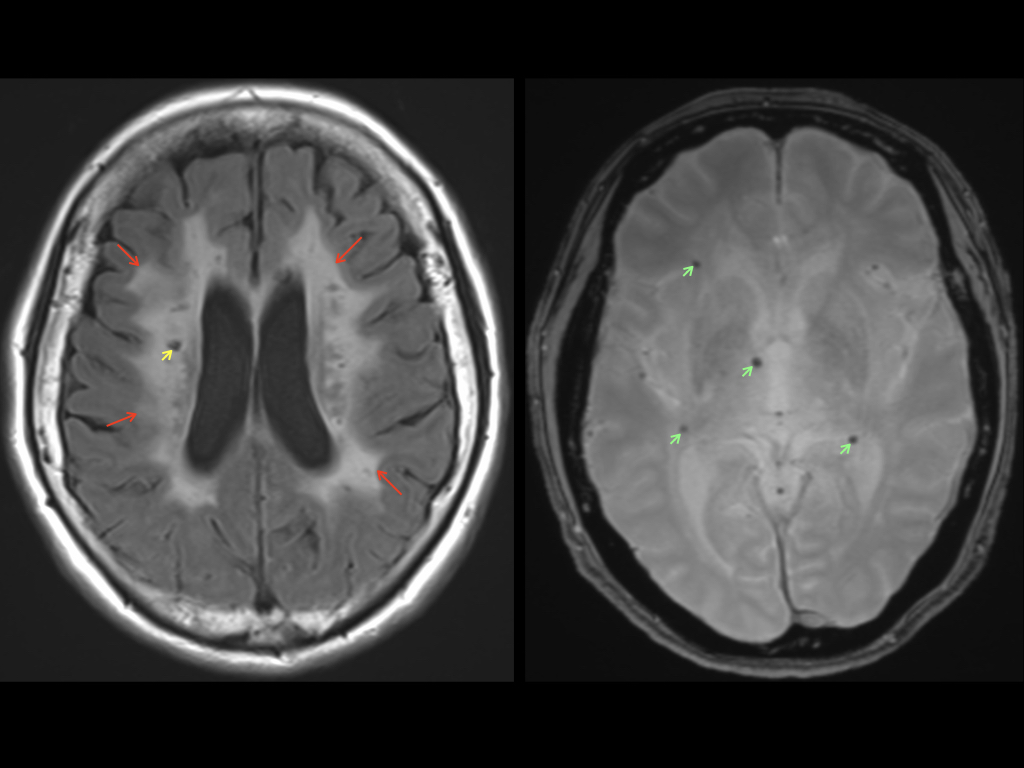

コラム | 岐阜大学大学院医学系研究科脳神経内科学分野, 脳血管の分子病態研究 | 研究紹介 - 新潟大学脳研究所 脳神経内科,

脳血管の分子病態研究 | 研究紹介 - 新潟大学脳研究所 脳神経内科, 朝倉書店『内科学』(第12版)デジタル付録,

結節性硬化症の脳病変のCT,MRI画像診断は?, 精神科治療学 32巻8号(2017年8月発行) 上田淳哉,袖長光知穂,「脳のMRI」細矢 貴亮 / 興梠 征典 / 三木 幸雄定価: ¥ 15000#細矢貴亮 #細矢_貴亮 #興梠征典 #興梠_征典 #三木幸雄 #三木_幸雄 #本家族に小型犬がおります。【裁断済】小児・成育循環器学 改訂第2版。喫煙者はおりません本のコンディションは価格に反映しているつもりです。病気がみえる⭐️11〜15冊セット⭐️送料込み。コンディションに質問がある方はご連絡ください。新 呼吸器専門医テキスト(改訂第2版)。